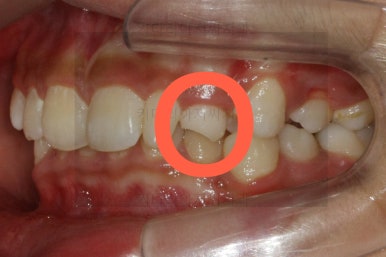

그 다음 문제는 왼쪽 송곳니 부분(붉은색 동그라미)이 유치가 남아있고, 영구치가 매복되어 있는 경우였어요.

화살표를 보시면 송곳니가 나오지 못하고 뼈속에 묻혀 있는 것을 볼 수 있습니다.

이를 "매복치" 혹은 "매복치아" 라고 표현하는데 이넞ㅂ한 치아들의 뿌리를 녹인다거나 아예 다른 방향으로 간다거나 하는 문제가 생길 수 있기 때문에 조기에 발견하고 치료를 해줘야 합니다.

상태를 보면 옆에 있는 안그래도 작은 왜소치의 뿌리를 건드리는 양상으로 있어서 좀 더 정밀한 3차원 CT를 찍어 보기로 했습니다.

이렇게 정확한 위치를 파악해보니 다행히 인접한 치아에 안좋은 영향을 주고 있는 것은 아니었고 어부바처럼 겹쳐있기만 했어요.